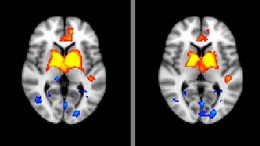

The Debrief: Standing up against bipolar disorder

The 5.7 million American adults living with bipolar disorder are about to get some major-league help: a nationwide coalition of expert institutions designed to collectively evaluate patients and determine…